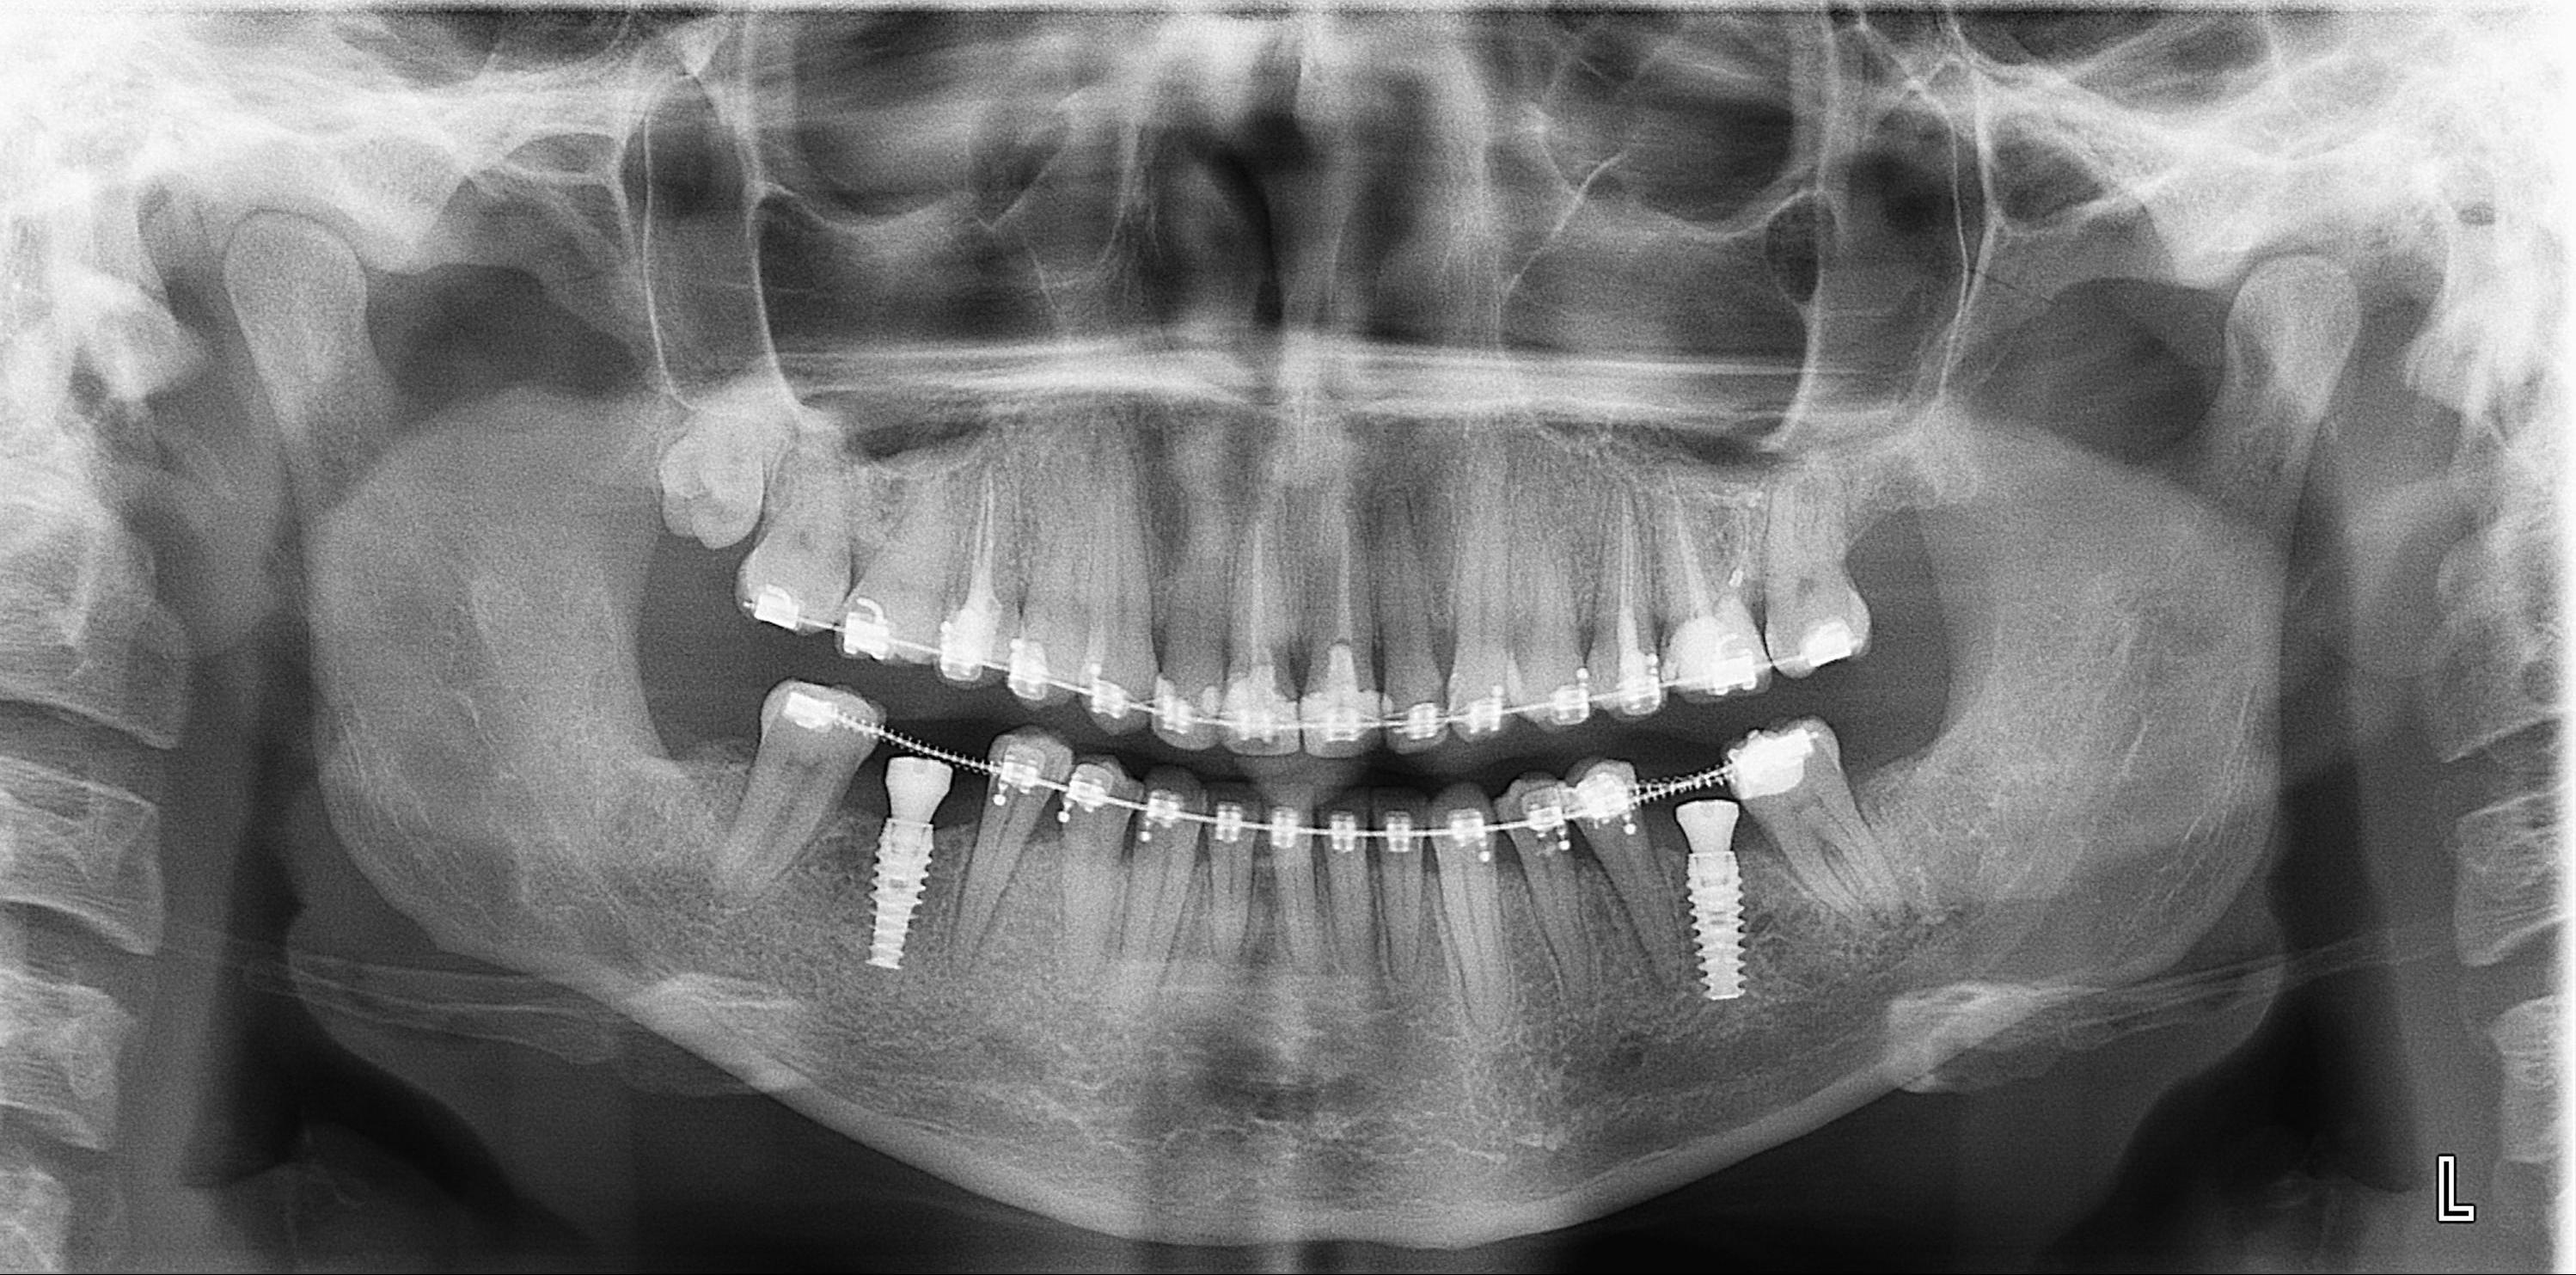

Фотографии ортопантомограмм и работ Родена